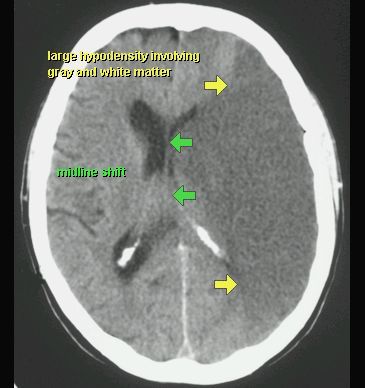

UDAR NIEDOKRWIENNY MÓZGU (ZAWAŁ MÓZGU)

TK